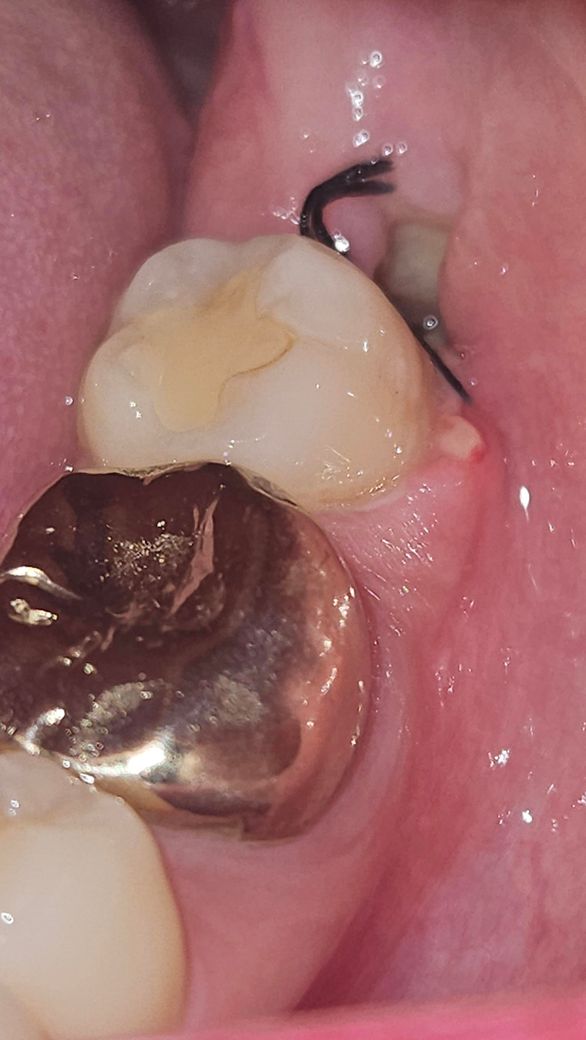

사진은 저게 최대고, 발치 구멍이 작은건지 안까지는 빛을 비춰도 잘 보이지 않네요. 드라이소켓 전조증상이 있을까요? 사진을 봤을 때 드라이소켓일 가능성이 높은가요? 앞에 구내염 때문에 이렇게까지 아플 수가 있나요? 만약 드라이소켓이라면 치료 방법은 무엇이고 치료의 고통 정도는 어느정도일까요?

• 3번 째 사진

사진을 봤을 때 드라이소켓일 가능성은 별로 높아보이지 않으며 통증은 견디기 힘든정도입니다.